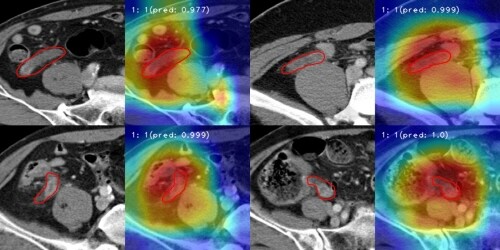

| ▲ 국내 의료진이 컴퓨터단층촬영(CT) 영상을 분석해 충수염을 자동 진단하는 인공지능(AI) 모델을 개발했다. (사진=한림대의료원 제공) |

한림대성심병원 연구팀이 개발한 이 AI 모델은 CT 영상을 실시간으로 관찰해 대장염, 말단회장염, 상행결장게실염 등 충수염과 임상적으로 유사한 질환을 걸러내고 충수염만을 정확하게 진단하는 것이 가능하다.

이후 충수염 환자 1839명, 충수염이 아닌 것으로 진단받은 1782명의 데이터를 걸러내고 ‘3D 컨볼루션 신경망(Convolutional Neural Network, CNN)’을 활용한 모델에 학습시켰다.

학습을 마친 AI모델의 충수염 진단 정확도는 89.4%로 나타났다. AI모델의 성능을 평가하는 데 사용하는 ‘곡선하면적(Area Under the Curve, AUC)’ 점수는 0.890으로 나타나 실제 임상에 적용할 수 있는 우수한 결과를 보였다.

조범주 의료인공지능센터장은 “이번 AI는 기존 모델들과 달리 3차원 CT영상을 입체적으로 인식했다는 점에서 의의가 있다”고 했다.